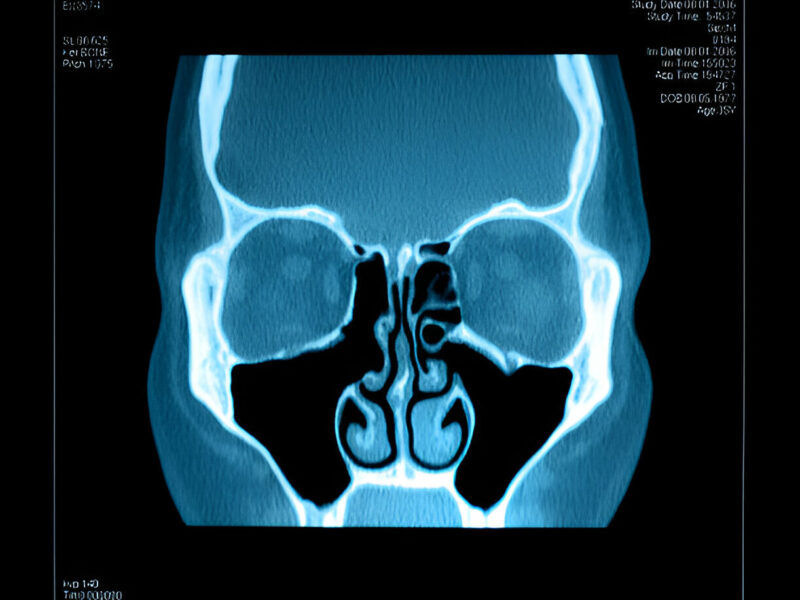

- Structural Issues: Deviated septum, nasal polyps, or other structural problems in the nasal cavity can block proper drainage, leading to sinus infections.

- Image-Guided Surgery: Advanced imaging techniques help surgeons precisely target affected areas with minimal damage to surrounding tissues.